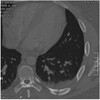

What pathology is seen here?

Bronchiectasis ## Footnote -Seeing cysts (advanced) -Fibrosis throughout the lungs

Bronchiectasis ## Footnote -Airway very dilated -Walls are normal thickness

Bronchiectasis ## Footnote -Signet ring appearance (ring is the bronchus, stone sitting on the ring is the blood vessel beside)